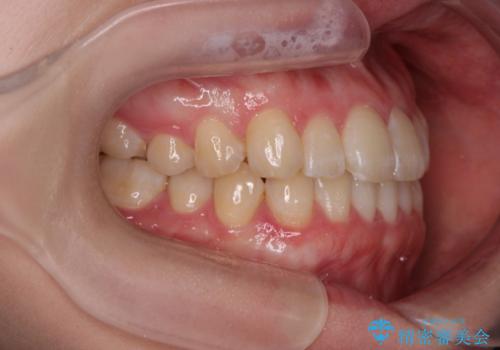

最新の症例

Latest cases